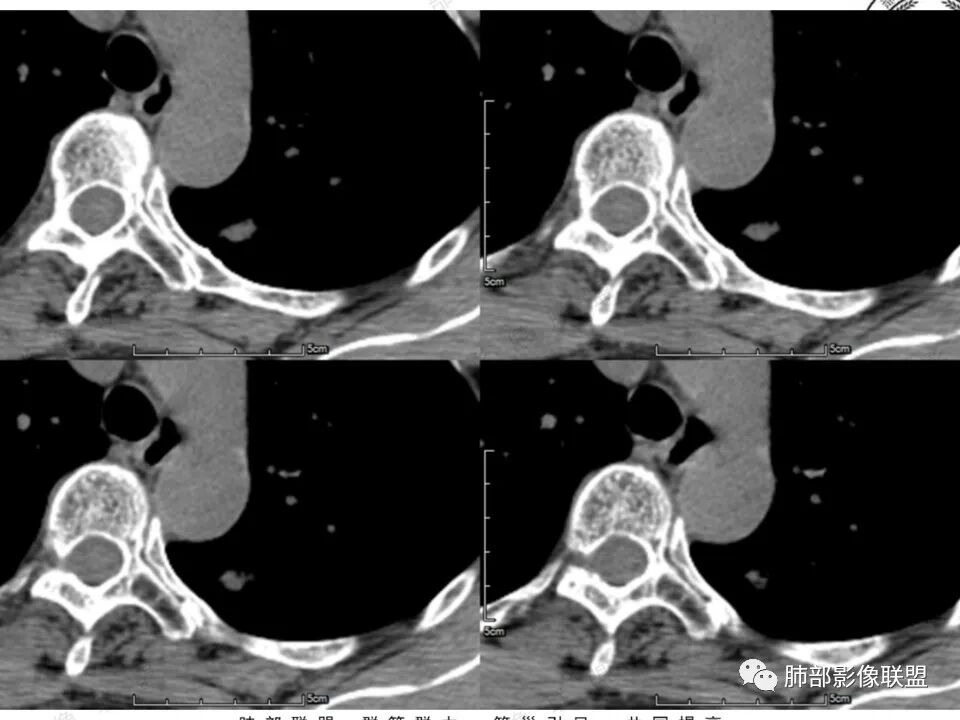

左肺上叶尖后段实性结节,边缘有清晰磨玻璃,胸膜有牵拉凹陷,明显强化,CT值超过主动脉,考虑血管畸形(周围磨玻璃可能是出血),鉴别IAC(影像表现符合,强化不符)

患者中年女性,体检发现。胸部CT:左肺上叶后段长条形结节灶,边缘光滑,边界清楚,见分叶、毛刺、胸膜牵拉及平直征象。增强明显强化,内可见血管增粗,综合考虑恶性病变,浸润性腺癌可能大,鉴别结核。

形态特征符合腺癌,就是这个强化幅值相对少见些,肺内其他高强化病变如类癌、血管瘤等形态又不甚符合。还是常规考虑浸润腺癌吧,当然抗炎复查这个过程还是要的。

41岁女性,左肺上叶不规则结节,边缘见似清非清的磨玻璃影,叶间裂牵拉。整体病灶边缘平直,强化明显。另左上叶外侧尚有一磨玻璃结节(蘑菇兄弟?),考虑炎性肉芽肿可能性大。强化太明显让人很纠结,会不会存在CD,但边缘又有磨玻璃影;腺癌、结核、隐球都没有见过强化这么明显的,强化程度与主动脉基本一致,不会是动静脉畸形吧。

没意见:

强化太猛,血管畸形?边缘磨玻璃区,腺癌?

功能学(高强化)形态学的取舍,形态学(ggo),高强化不能除外ca

形态上看肯定不敢排除ca,就是强化这点,以往没认识到

晨读反思:1.边缘磨玻璃还是比较清楚;2.有收缩力;3.强化明显提示内部有血管,说明破坏力不强。

1.中年女性,体检发现;2.左肺上叶后段长条形结节灶,边缘有膨隆,也有收缩,腺癌和炎性结节都可以,但是周围见边界清楚磨玻璃影强烈提示腺癌可能性。3.显著强化的肺结节,无论如何都应当引起我们的高度重视!尽管炎性病灶和新生物都可以,尽管强化程度不能作为诊断癌肿的依据。

4.本例结节强化程度明显低于主动脉,也缺乏血管畸形的典型的迂曲结构,血管畸形可能性不大。